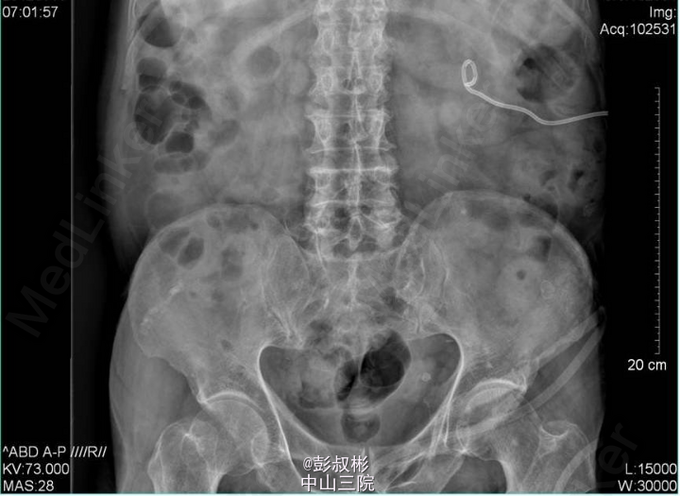

4、入院后处理:完善相关检查,考虑存在泌尿系梗阻引起的肾功能不全,于03-14行“B超引导下经皮肾穿刺造瘘术”, 03-16 复查生化十项:肌酐(酶法)151.000umol/L,尿素氮11.190mmol/L。3-15 3-18 KUB:盆腔左上部见一结节状高密度影,大小约为7mm×7mm。左肾区可见造瘘管影。 3-18于手术室全麻下行“左侧输尿管镜下钬激光碎石术”,术程顺利,术后予抗感染、补液、营养支持等对症治疗。于03-19复查生化十项:尿素氮6.550mmol/L,肌酐(酶法)103.600umol/L。复查KUB提示结石已清除,左肾造瘘管及双J管在位。